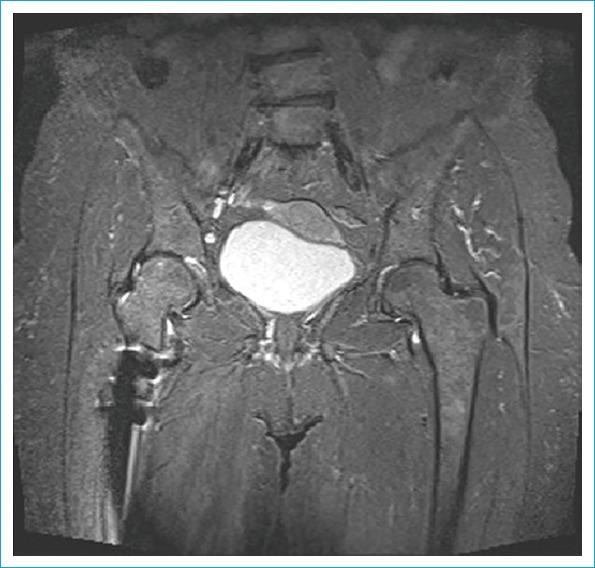

Developmental dysplasia of the hip (DDH) is still one of the biggest orthopedic problems in the world. Global poverty and refugee crises have led to it becoming a greater issue even in developed nations. Early diagnosis and effective treatment of DDH are required to prevent the possibility of arthrosis, limb shortening, pelvic asymmetry, and vertebral scoliosis. In late cases, surgery is the only choice for correction. Direct radiography has been used for many years and continues to have an important role, though ultrasonography is the primary source for early postnatal screening. Although magnetic resonance imaging (MRI) has become an important modality to provide sectional imaging in many cases, in late-period dysplasia, computed tomography (CT) and three-dimensional (3D) CT are preferred because it can more effectively demonstrate the cortical bony structures. The aim of this review was to demonstrate the effectiveness of 3D CT and multiplanar reconstruction based on previous studies.

发育性髋关节发育不良(DDH)仍然是全球最严重的骨科问题之一。全球贫困和难民危机导致即使在发达国家,这一问题也日益严重。为预防关节病、肢体缩短、骨盆不对称和脊柱侧弯的发生,需要对DDH进行早期诊断和有效治疗。在晚期病例中,手术是唯一的矫正选择。直接X线摄影已使用多年且仍发挥着重要作用,不过超声检查是出生后早期筛查的主要手段。尽管磁共振成像(MRI)在许多情况下已成为提供断层成像的重要方式,但在晚期发育不良中,计算机断层扫描(CT)和三维(3D)CT更受青睐,因为它们能更有效地显示皮质骨结构。本综述的目的是基于以往研究展示3D CT和多平面重建的有效性。